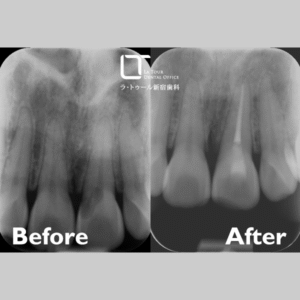

ダイレクトボンディング・30代(男性)|「奥歯の虫歯を一度の治療できれいに治したい」

治療内容 ダイレクトボンディング 施術費用 44000円×2本 通院回数 1回 通院期間 メリット 歯を削る量を最小限に抑えながら、自然な色味や形に仕上げることができます。1回の治療で完了するケースが多く、保険適用外の自由診療ではありますが、セラミック治療に比べて費用を抑えることが可能です。 リスクと副作用 強い衝撃や過度な力が加わると、欠けたり割れたりする恐れがあります。経年劣化により、変色や着色、摩耗が生じる可能性があります。症例によっては適応できない場合があります。 ダイレクトボンディングの治療例です。奥歯の虫歯を、一度の治療できれいに治したいとの […]